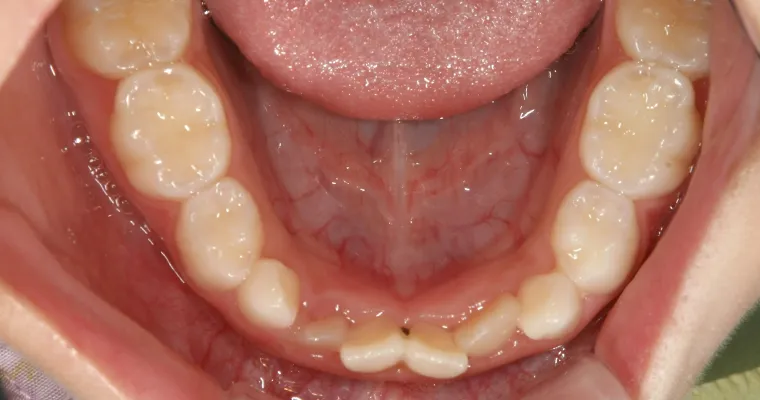

下顎咬合面観

BEFORE

AFTER